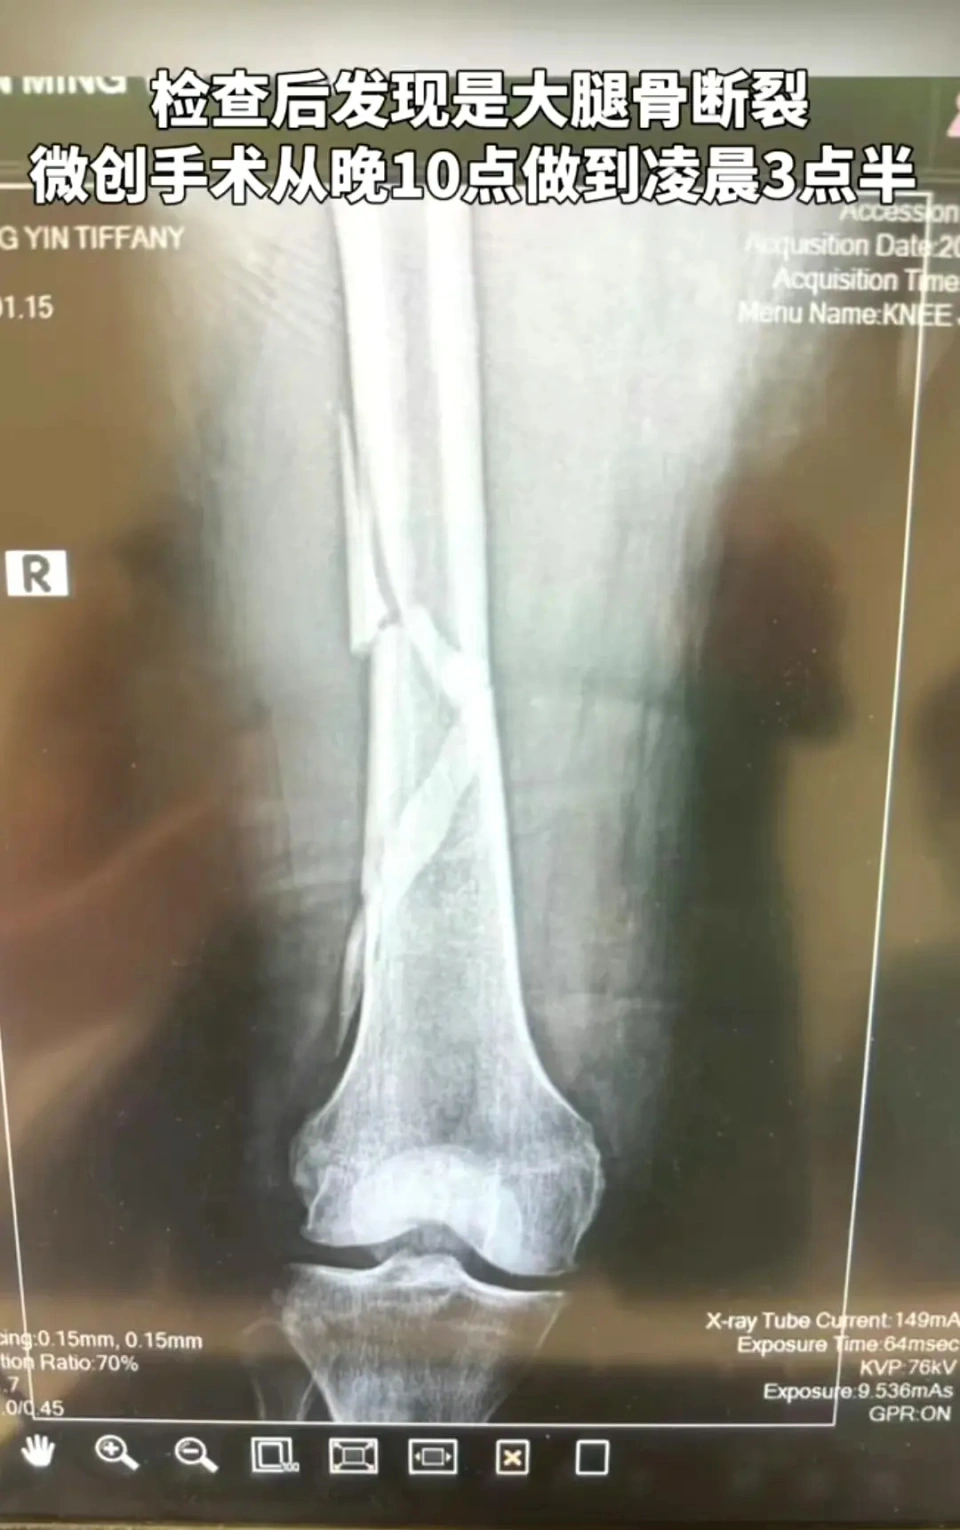

克日67岁的向太突然变得安静了起来,不但很少出现在大众视野,就连直播都很少开。相较于向太的半隐退状态,她的儿子儿媳倒是综艺上个不绝,话题度和讨论度更是高居不下,此中儿子向佐更是依附一己之力贡献了浩繁经典名局面。 26日下战书向太发视频自曝,本身不慎在浴室跌倒导致大腿骨折,并配文称“大腿骨断裂,凡间痛楚似乎一样都没放过我。但我依然选择刚强面临,笑对波折,笑对人生。渴望各人多多注意安全,掩护好本身。” 这个消息真的太突然了,就在26日中午向太还发文让各人谨防AI诈骗。她体现对方AI换脸了向佐的脸,本身不但没认出来还和对方聊得很开心。末了她还提示各人肯定要警惕AI换脸科技,谨防被换脸的亲朋诈骗。 真是世事无常,向太前脚还在提示各人谨防被骗,后脚就传出了跌倒的消息。 在看到向太大腿骨折后,很多网友纷纷留言批评称,向太真的不适当凡间痛楚,这个词是给老百姓用的。房子太大了,喊个人也必要半个小时才华听到。如果郭碧婷知道向太受伤了,肯定不会继承录制浪姐了,看到婆婆伤得这么重,郭碧婷肯定哭得泣不成声。 向太体现,她是由于在沐浴的时间,不警惕踩到了没有防滑垫的地方,导致整个人身段倾斜重心不稳,加上寻常松弛锻炼,身段有些圆润,以是不慎跌倒在了浴室中。 别的向太还体现,其时整个人都是懵的,一度痛到站不起来。由于浴室隔音很好,即便向太冒死呼救,但照旧叫天不灵,叫地不应,直到半个小时以后才被人发现。 向太称,本身很担心救护车抵家里的声音会造成不实的推测和报道,以是为了不占用公共资源,她第一个夜晚全程都待在浴室中,哪都不敢去。 直到第二天早上,向太才请了家庭医生,在整个过程中向华强也不绝守卫在她身旁。 到了医院后,颠末专业查抄发现向太是大腿骨断裂,微创手术从晚上十点不绝连续到破晓3点半,整个晚上她就睡了一个小时。 向太透露,她的大腿里有一根很长的钛金属管和四根髓钉,现在也是一位名副实在的“钢铁女侠”。 向太体现本身做完手术第一天就下床了,她身穿长裙戴着帽子,团体打扮贵气又时尚,即便受伤也要时候保持面子。向太称,固然全愈过程很痛楚,但是也要在黄金期的时间去积极全愈规复正常。有点小波折也无所谓,要笑对波折。 伤筋动骨一百天,未来将会有很长一段时间都看不到向太的身影了,向佐和郭碧婷在得知这个消息后,肯定是急得不得了,反面的综艺录制大概也会受到影响。渴望向太好好修养,早日全愈! |